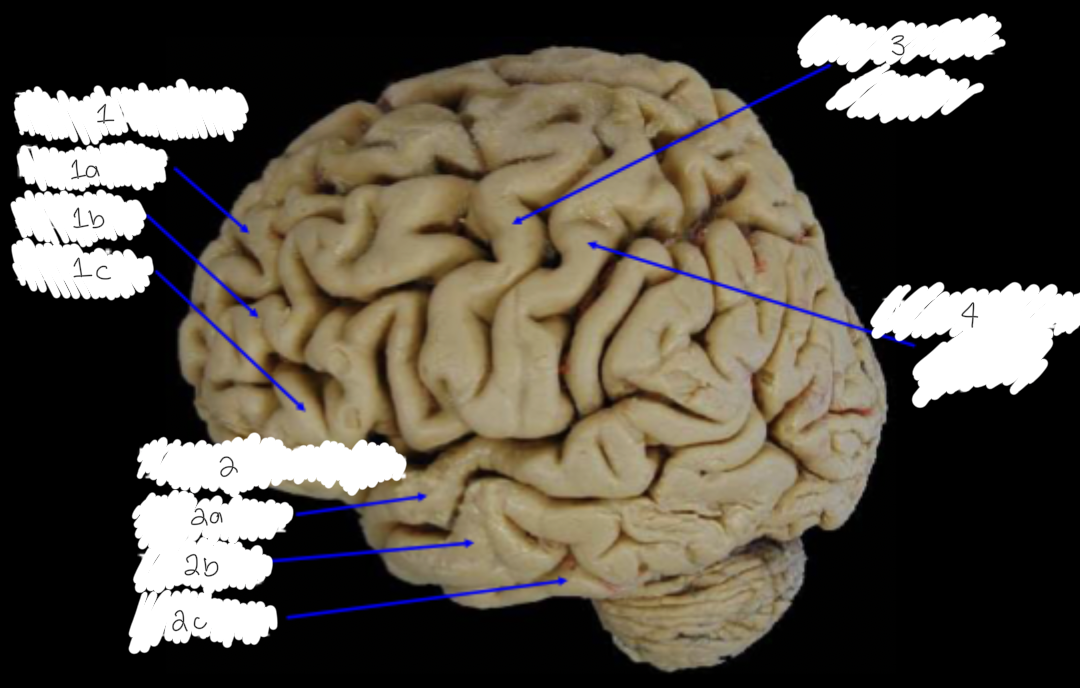

Label this diagram

1: frontal gyri: a) superior, b) middle, c) inferior

2: temporal gyri: a) superior, b) middle, 3) inferior

3: precentral gyrus

4: postcentral gyrus